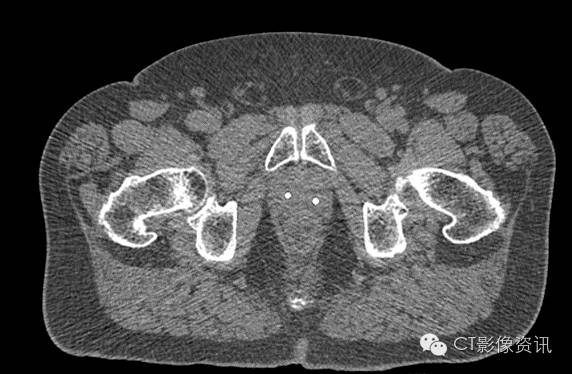

牙齿填塞物

Without MAR

With MAR

Smart MAR 有效地消除了牙齿填充物导致的伪影,周边清晰,利于观察。